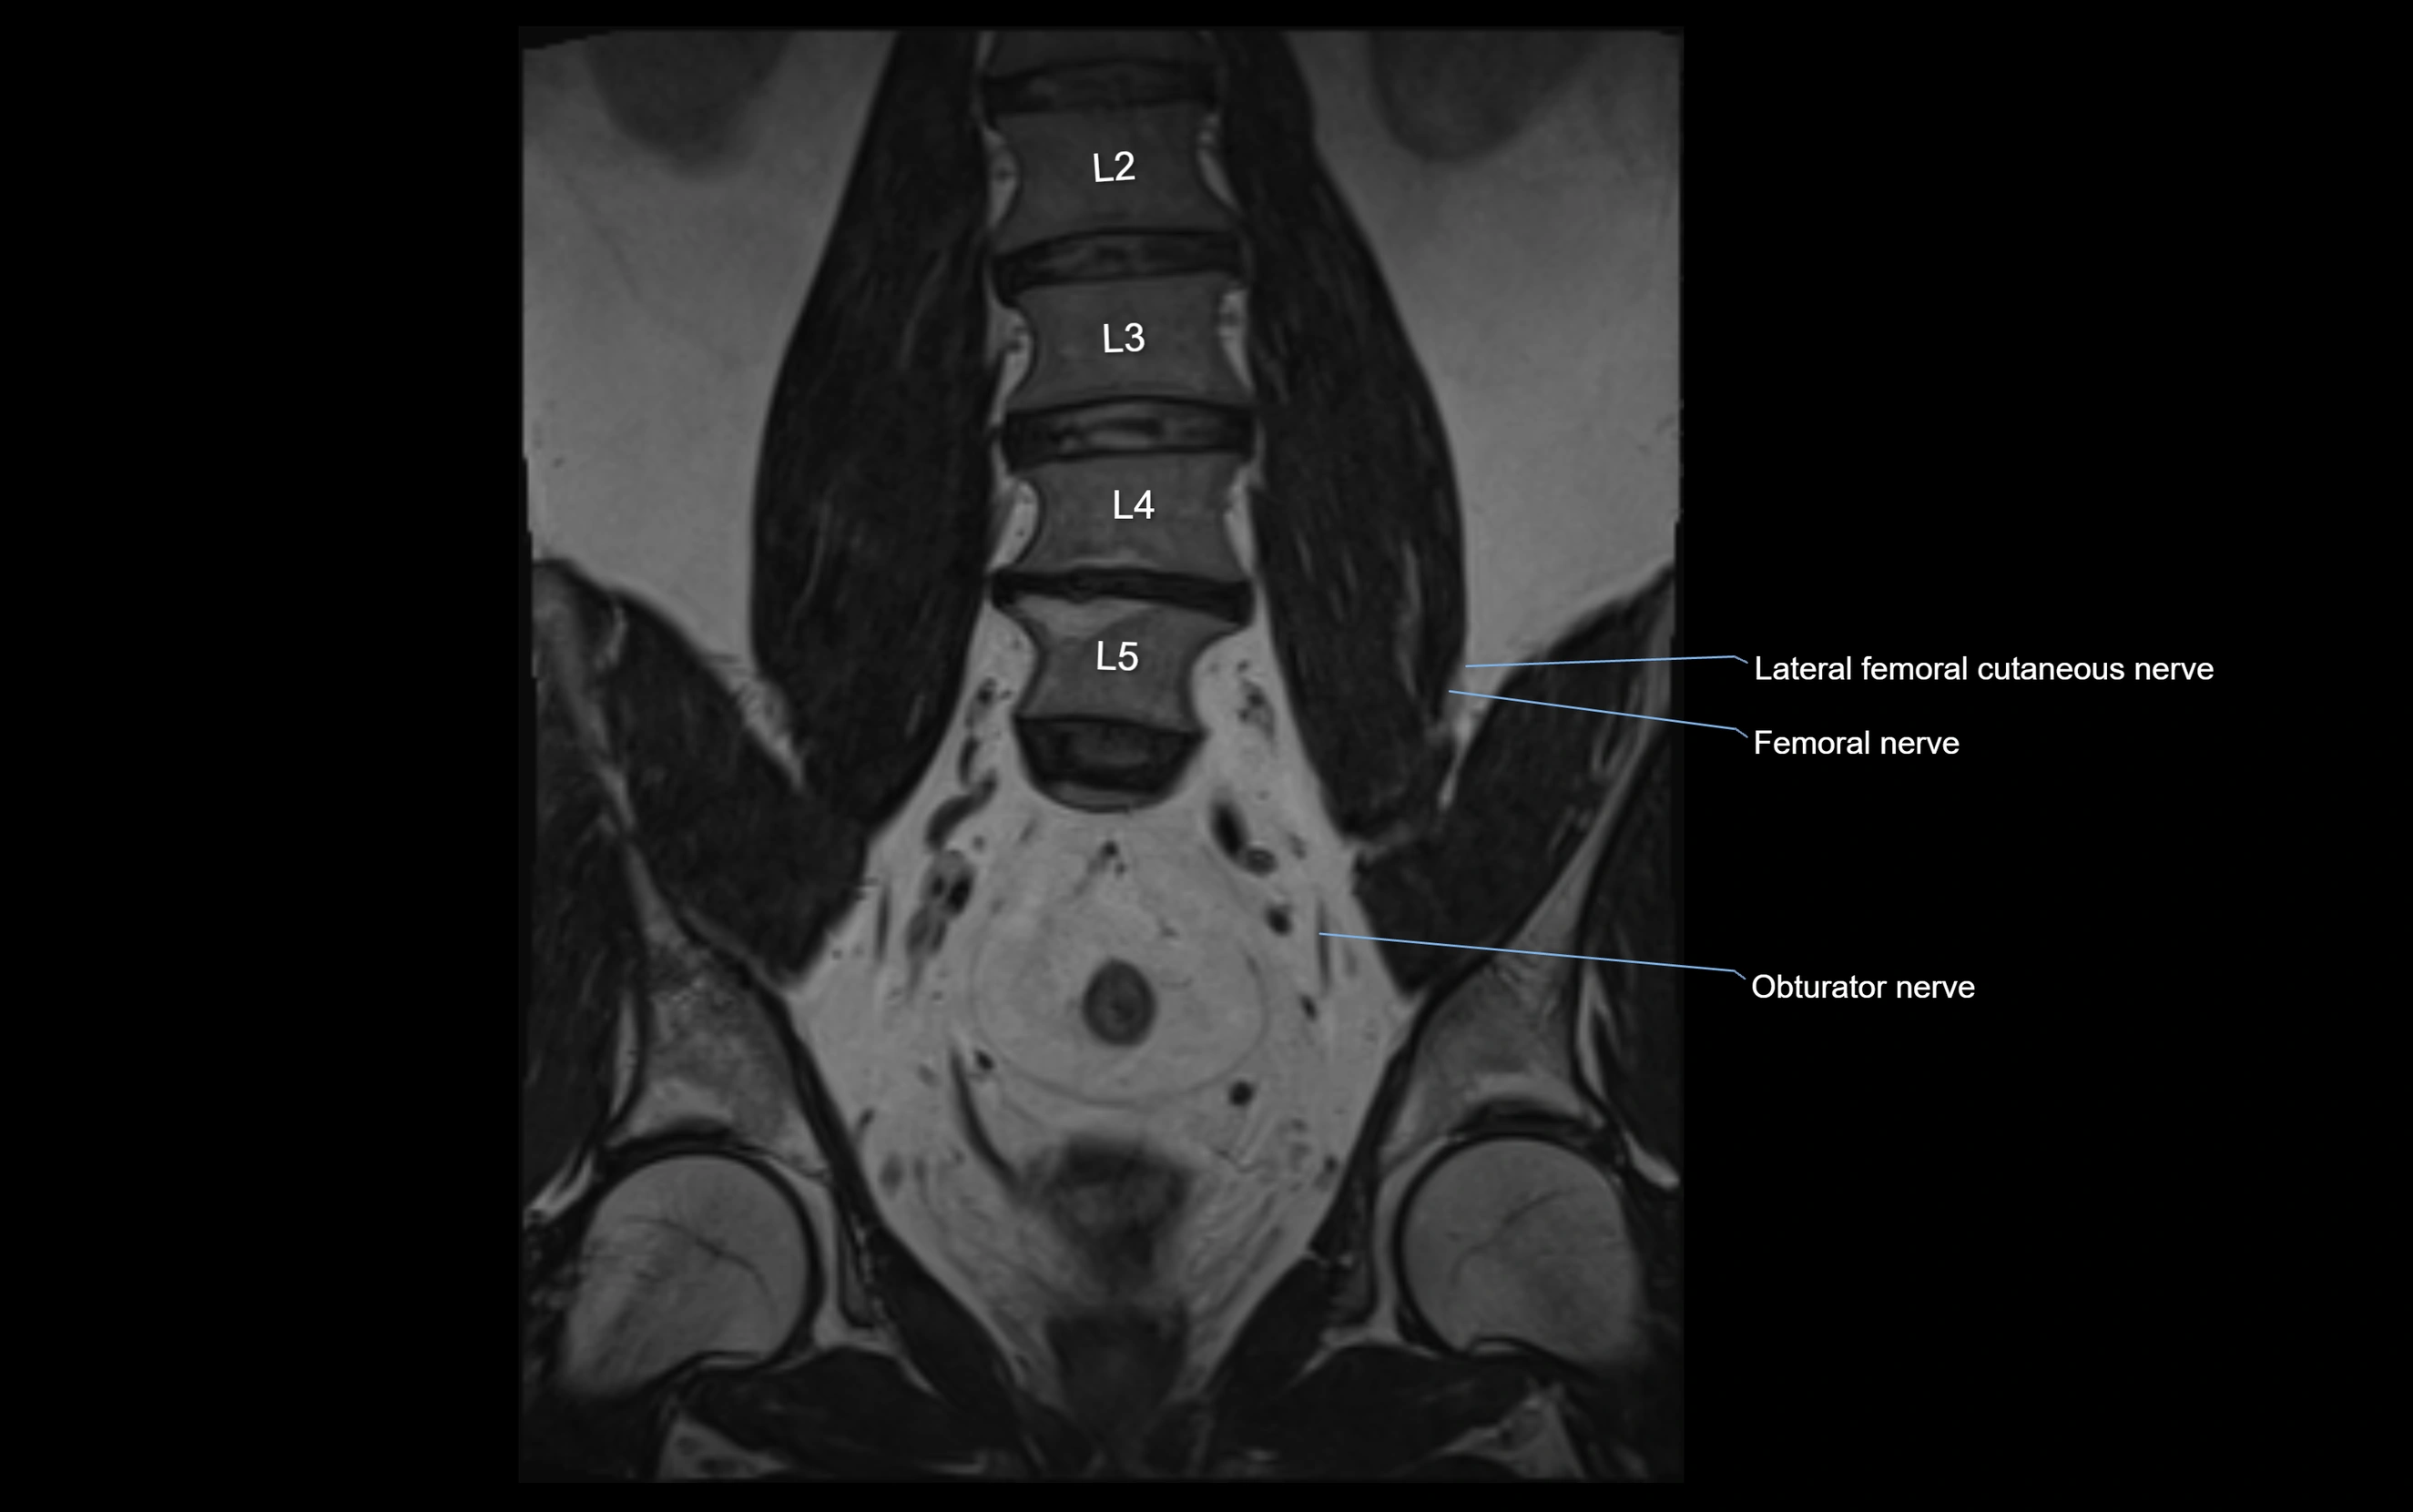

MRI image

image